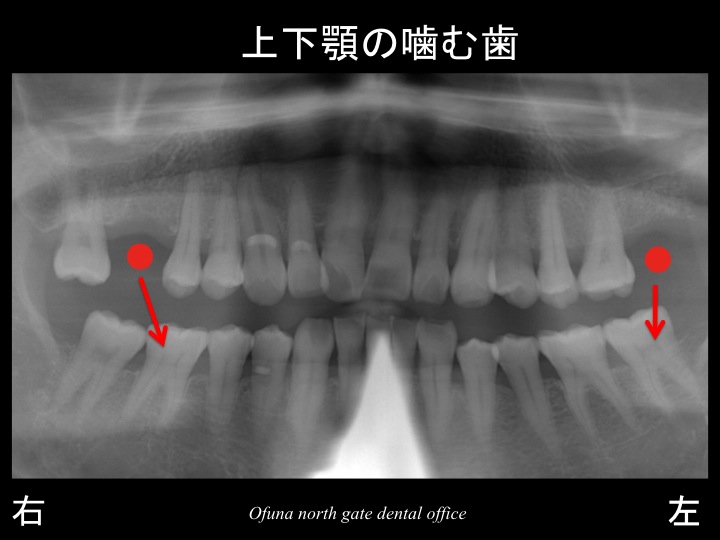

以下のレントゲンが初診時になります。

以下の●:赤丸が歯がない部分になります。

下のレントゲン写真は、上下顎の歯が噛み合っている位置を表したものです。